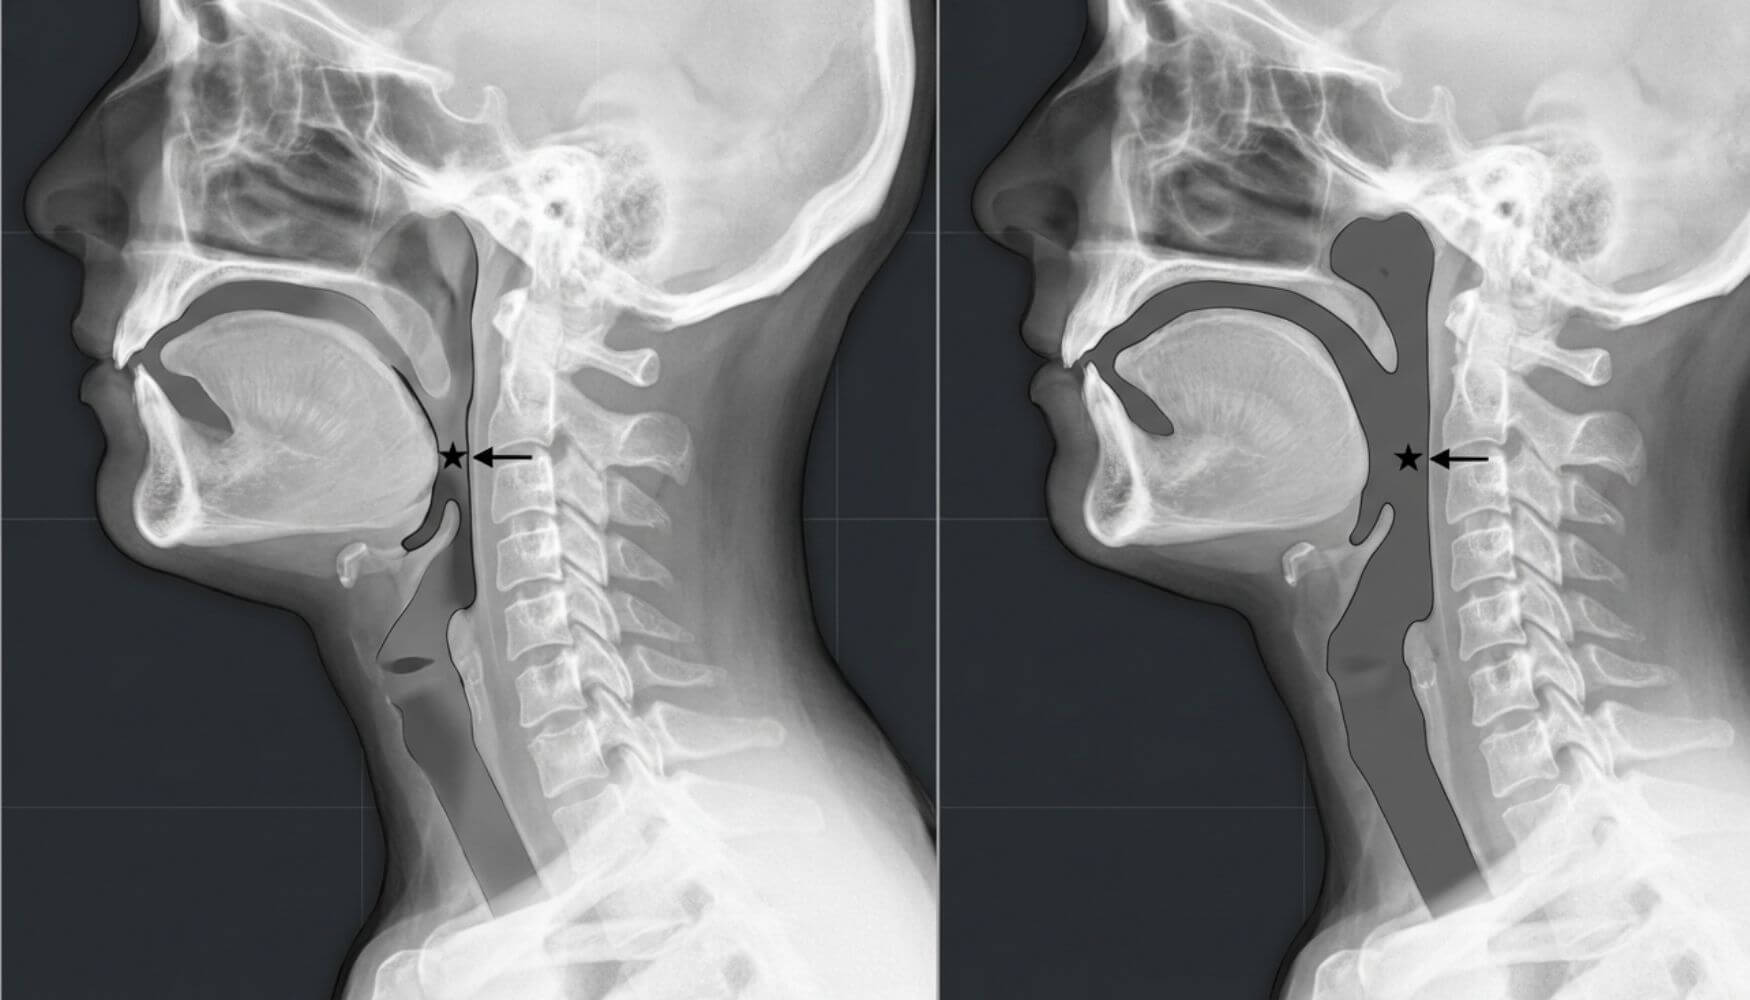

Every night, your neck falls into a forward curve → your airway folds in on itself → breathing stops.

When you lie on a regular pillow, your head tilts forward and down.

This bends your neck at an acute angle, compressing your airway.

Regular pillows force your head downward and compress your airway—no matter your body weight, fitness level, or age.

86% of sleep apnea is position-dependent. Meaning, your airway isn't randomly collapsing...

...it collapses because your head drops into the wrong angle.

When sleep apnea patients were positioned with proper cervical spine alignment, 78% showed improved breathing patterns.

Here's what sleep doctors discovered: When the cervical spine aligns naturally, your airway has space to stay open without machines, masks, or dental devices. Most people have no idea their pillow is the real problem, and the real solution.